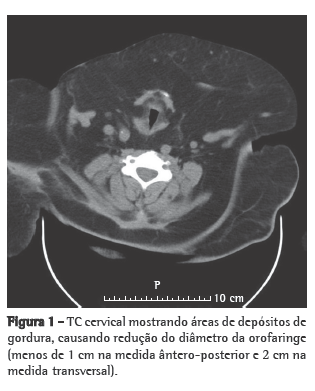

As condições clínicas do paciente melhoraram progressivamente, com a subsequente redução das pressões BiPAP e do uso do ventilador, que foi interrompido no 6º dia de internação em virtude do aparecimento de ulcerações faciais causadas pela máscara nasal. Durante a primeira noite sem ventilação não-invasiva, houve longos períodos de dessaturação de oxigênio (SpO2 < 88%) e ronco. O paciente foi então submetido à TC cervicofacial (Figuras 1 e 2) e a um estudo cardiorrespiratório do sono.

O estudo do sono levou aproximadamente 8 h, revelando grave apneia obstrutiva do sono (índice de apneia-hipopneia: 37 eventos/h; índice de apneias obstrutivas: 29 eventos/h; mediana de saturação periférica de oxigênio durante o sono: 88%; índice de dessaturação de oxigênio: 51%/h; e SpO2 mínima: 51%). A TC revelou várias áreas de depósitos de gordura no mediastino, causando uma redução no calibre da traqueia de 1 cm transversalmente e 4 cm ântero-posteriormente. A titulação da continuous positive airway pressure (CPAP, pressão positiva contínua nas vias aéreas) foi realizada na segunda noite, e o paciente recebeu alta. Em casa, o paciente permaneceu em ventilação BiPAP (EPAP: 8 cmH2O; IPAP: 16 cmH2O), realizada através de almofadas nasais (Figura 3).